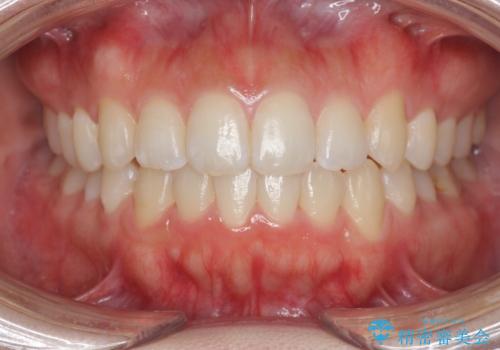

前歯のすれ違い インビザラインで行うマウスピース矯正

- 前歯のガタつき、でこぼこ、前後が逆になっている噛み合わせの改善を求めて来院されました。

治療の装置が目立たず歯ブラシのしやすいマウスピース矯正インビザラインでの治療を計画します。

20時間/日の装用時間をしっかりと守っていただき、きれいな歯並びを手に入れることができました。